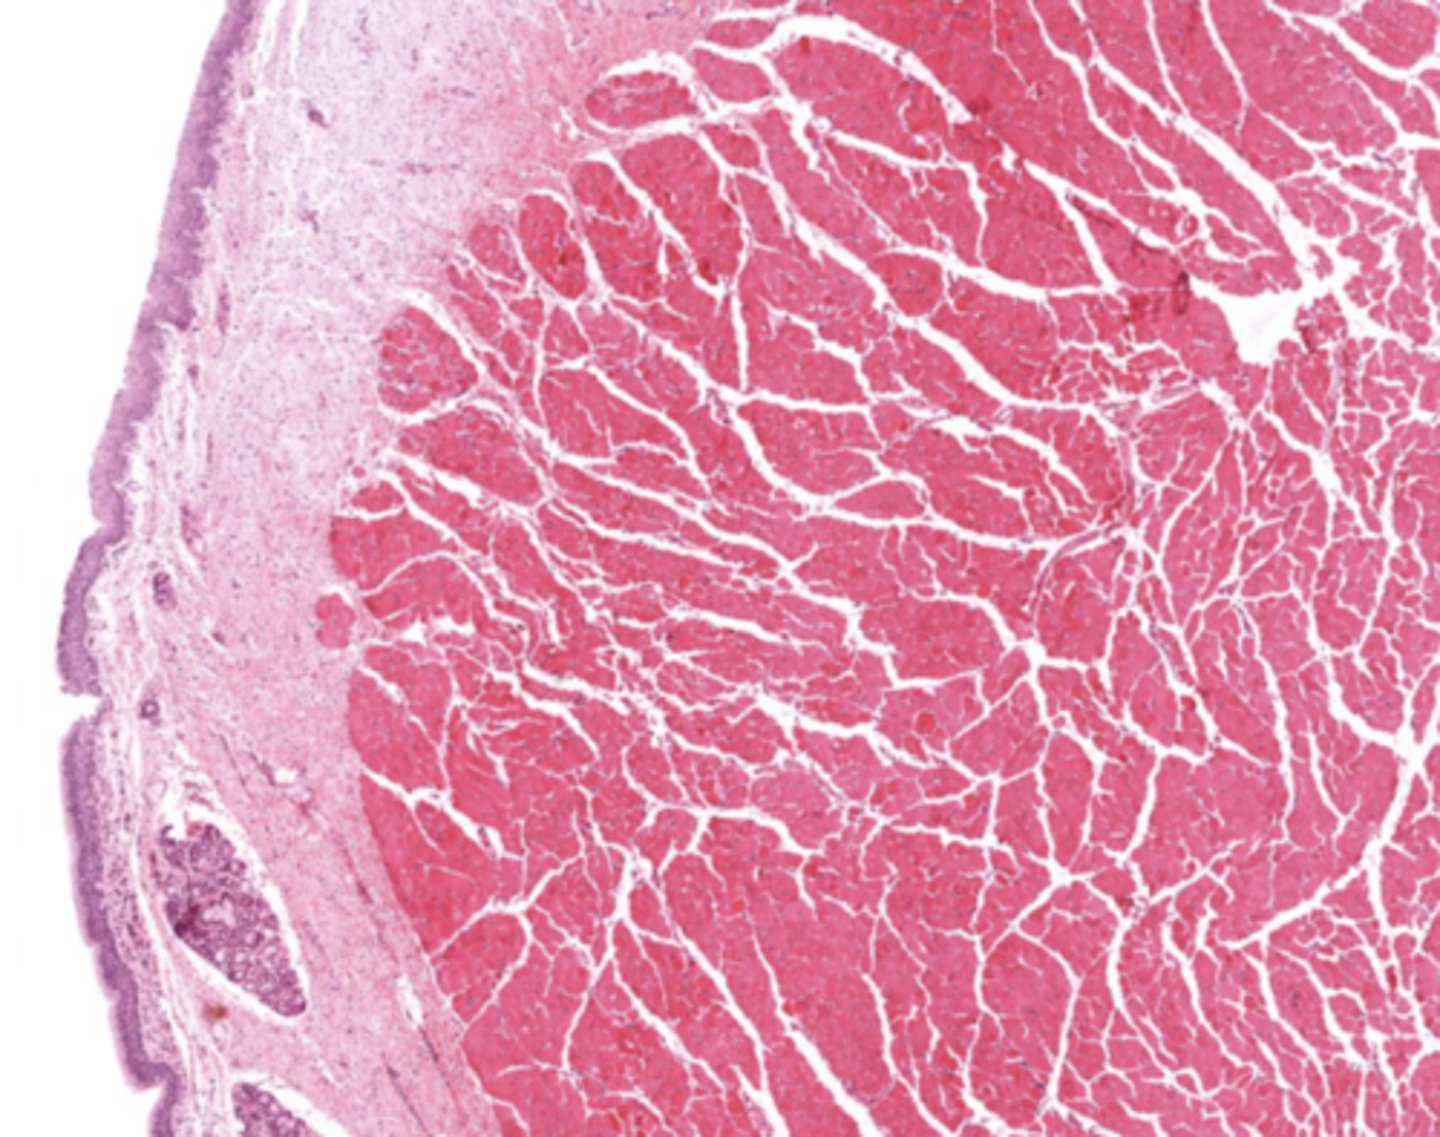

What muscle is found in the true vocal cords?

Vocalis muscle (skeletal muscle).

What forms the vocal ligament?

A band of elastic fibers.

What epithelium lines the true vocal cords? and why is it this specific epithelium?

Stratified squamous non-keratinized epithelium

so we can speak if we had any other lining the voice will be distorted

Why is Reinke's space clinically important?

No lymphatic vessels -> Reinke's edema.

True cords of the larynx

Identify the image